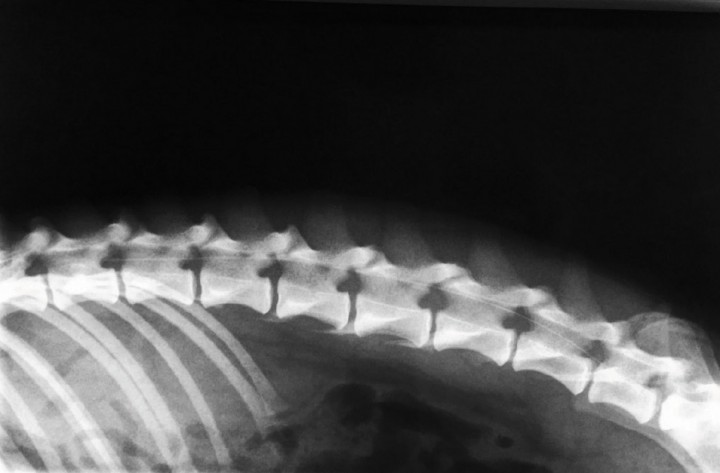

La administración epidural de bupivacaína y morfina resulta actualmente una práctica común en la clínica de pequeños animales, y resulta adecuada en este tipo de intervenciones. Dada la dificultad que supone realizar la punción epidural entre las vértebras L1 y L2 (punto recomendado para que se produzca la distribución del anestésico local en la columna torácica), en este paciente se optó por la introducción de un catéter epidural (Fig. 4), desde un abordaje lumbo-sacro, llevando la punta del catéter hasta el nivel deseado L1-L2 (Fig. 5). De esta forma se pudo realizar el depósito de los fármacos en el punto de interés, sin efectuar la punción epidural en porciones más craneales del canal vertebral. Las concentraciones y dosis empleadas fueron: bupivacaína 0,25 % (0,05 ml/kg) y morfina 1 % (0,1 mg/kg). Además, la cateterización epidural permitió la administración de anestesia regional durante las siguientes 24 h tras la intervención.

<p>Radiografía de contraste del catéter epidural llevado hasta L1-L2.</p>

Figura 5

Radiografía de contraste del catéter epidural llevado hasta L1-L2.

Tradicionalmente la anestesia epidural se ha realizado entre L7 y S1, una técnica de una simplicidad relativa que puede aprenderse con cierta rapidez. En las últimas décadas han sido descritos diferentes abordajes y técnicas que permiten el depósito de los AL más cerca de los nervios diana en el canal vertebral.[ Otero PE, Campoy L. Epidural and Spinal Anesthesia. En: Campoy L & Read M: Small Animal Regional Anesthesia and Analgesia, Ames, Wiley-Blackwell, 2003; 227-260. [PMC] ] El bloqueo anestésico de los nervios que aportan sensibilidad a la pared costal implica necesariamente administrar el AL en el canal vertebral a nivel de la columna torácica. Para ello, se recomienda la introducción de la aguja epidural entre las vertebras L1 y L2, dirigiendo el bisel cranealmente.[ Otero PE, Campoy L. Epidural and Spinal Anesthesia. En: Campoy L & Read M: Small Animal Regional Anesthesia and Analgesia, Ames, Wiley-Blackwell, 2003; 227-260. [PMC] ] Este abordaje es complicado, ya que el espacio intervertebral L1-L2 es de escasas dimensiones. Además, se corre el riesgo de punción accidental de la médula espinal. Como ya se comentó, el espacio L7-S1 es el más utilizado para efectuar epidurales, ya que presenta mayores dimensiones, lo que simplifica la punción. El empleo de catéteres epidurales resulta un procedimiento terapéutico de elección para la administración continua o en bolos de un fármaco. Así, su uso permite prolongar la actividad de los AL “tanto tiempo como se considere necesario”. Otra de sus ventajas radica en la posibilidad de introducir el catéter epidural en el canal vertebral y avanzar cranealmente hasta el punto que resulte clínicamente indicado. En este paciente se optó por la colocación de un catéter epidural a través de una punción lumbo-sacra convencional, para después llevarlo hasta L1-L2.